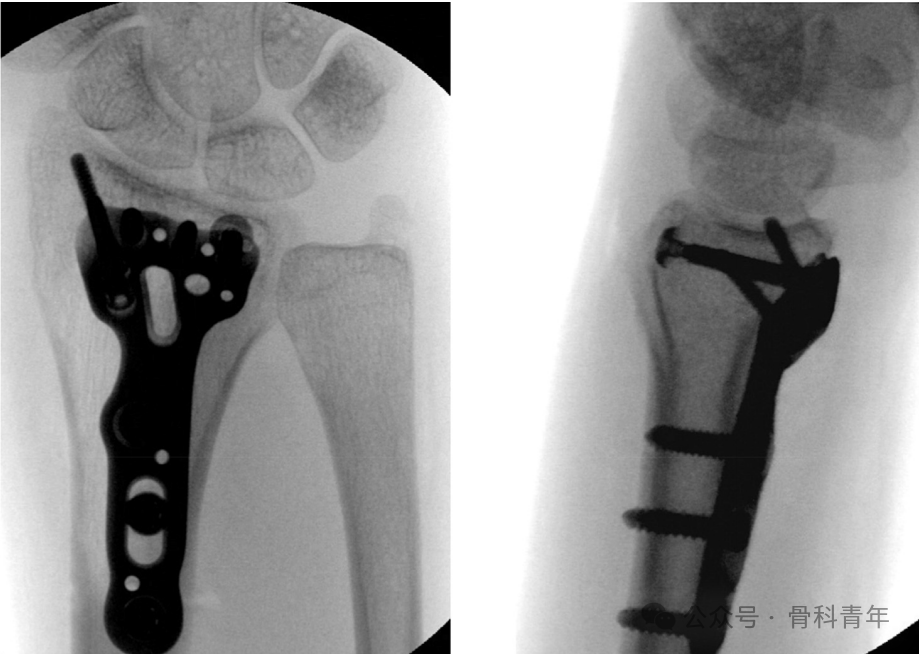

该手术方式的原理较为简单,首先,采用常规掌侧入路,钢板螺钉复位主要骨折块;在钢板螺钉固定后,经钢板定位孔或经钢板外,置入2枚1mm克氏针,自掌侧临时固定背侧骨块;